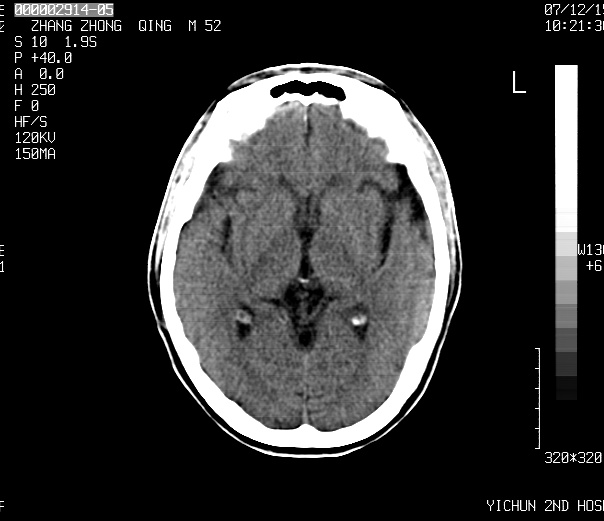

标题: CT11173:请会诊 男 52

1、四叠体脂肪瘤;

2、双侧额、顶部硬膜下积液。

头痛二年余,ct值-86.8hu.

考虑    四叠体池脂肪瘤。脑萎缩

1)四叠体池脂肪瘤.2)脑萎缩.

考虑:1、四叠池区脂肪瘤(比较常见)。

2、脑萎缩。